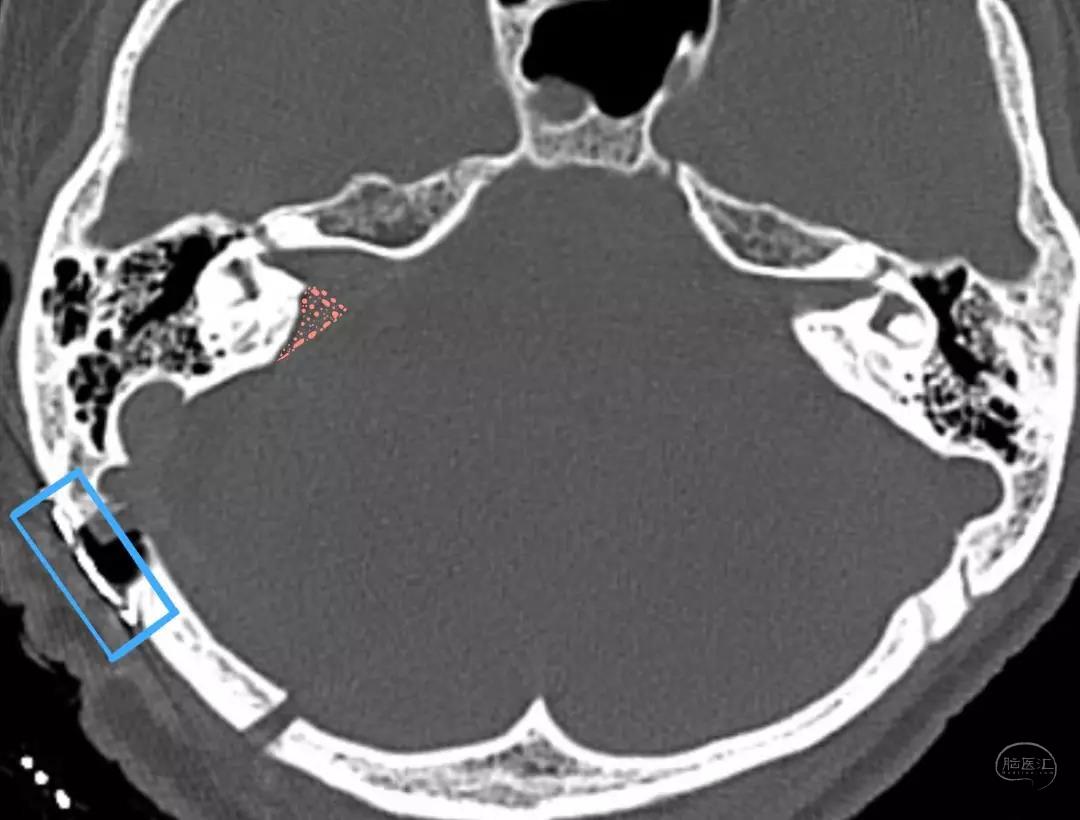

术前影像

术前影像资料

(肿瘤长入内听道内较深-9.1mm)

术前内听道扩大(右侧)

术后内听道

后半规管保留 骨瓣还纳

术前影像资料

肿瘤长入内听道内较深-10.3mm